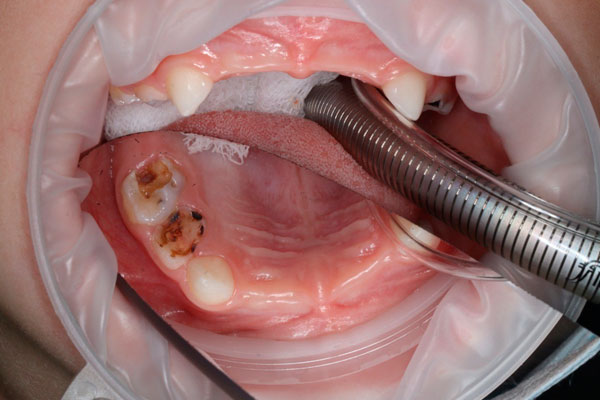

- Эксперт малоинвазивных технологии в детской стоматологии, лечение начального кариеса без бормашин

- Доктор владеет передовыми технологиями в лечении и восстановлении как молочных, так и постоянных зубов, обеспечивая эффективное и безопасное лечение;

- 2024 - APPD - "Пульпиты и периодонтиты на молочных зубах и постоянных зубах с несформированными верхушками"